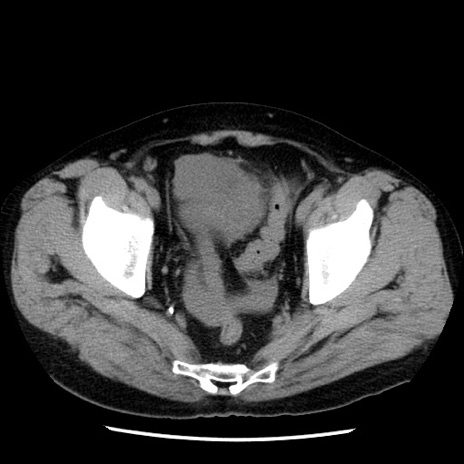

症例29(横断像)

【症例】40歳代男性

【現病歴】2日前から胃痛あり。徐々に周期的な激痛に変化した。本日になっても激痛があるため受診。

【身体所見】意識清明、BT 38-39℃台あり、腹部:膨満、やや硬、右下腹部に圧痛あり。

【データ】WBC 8500、CRP 23.26